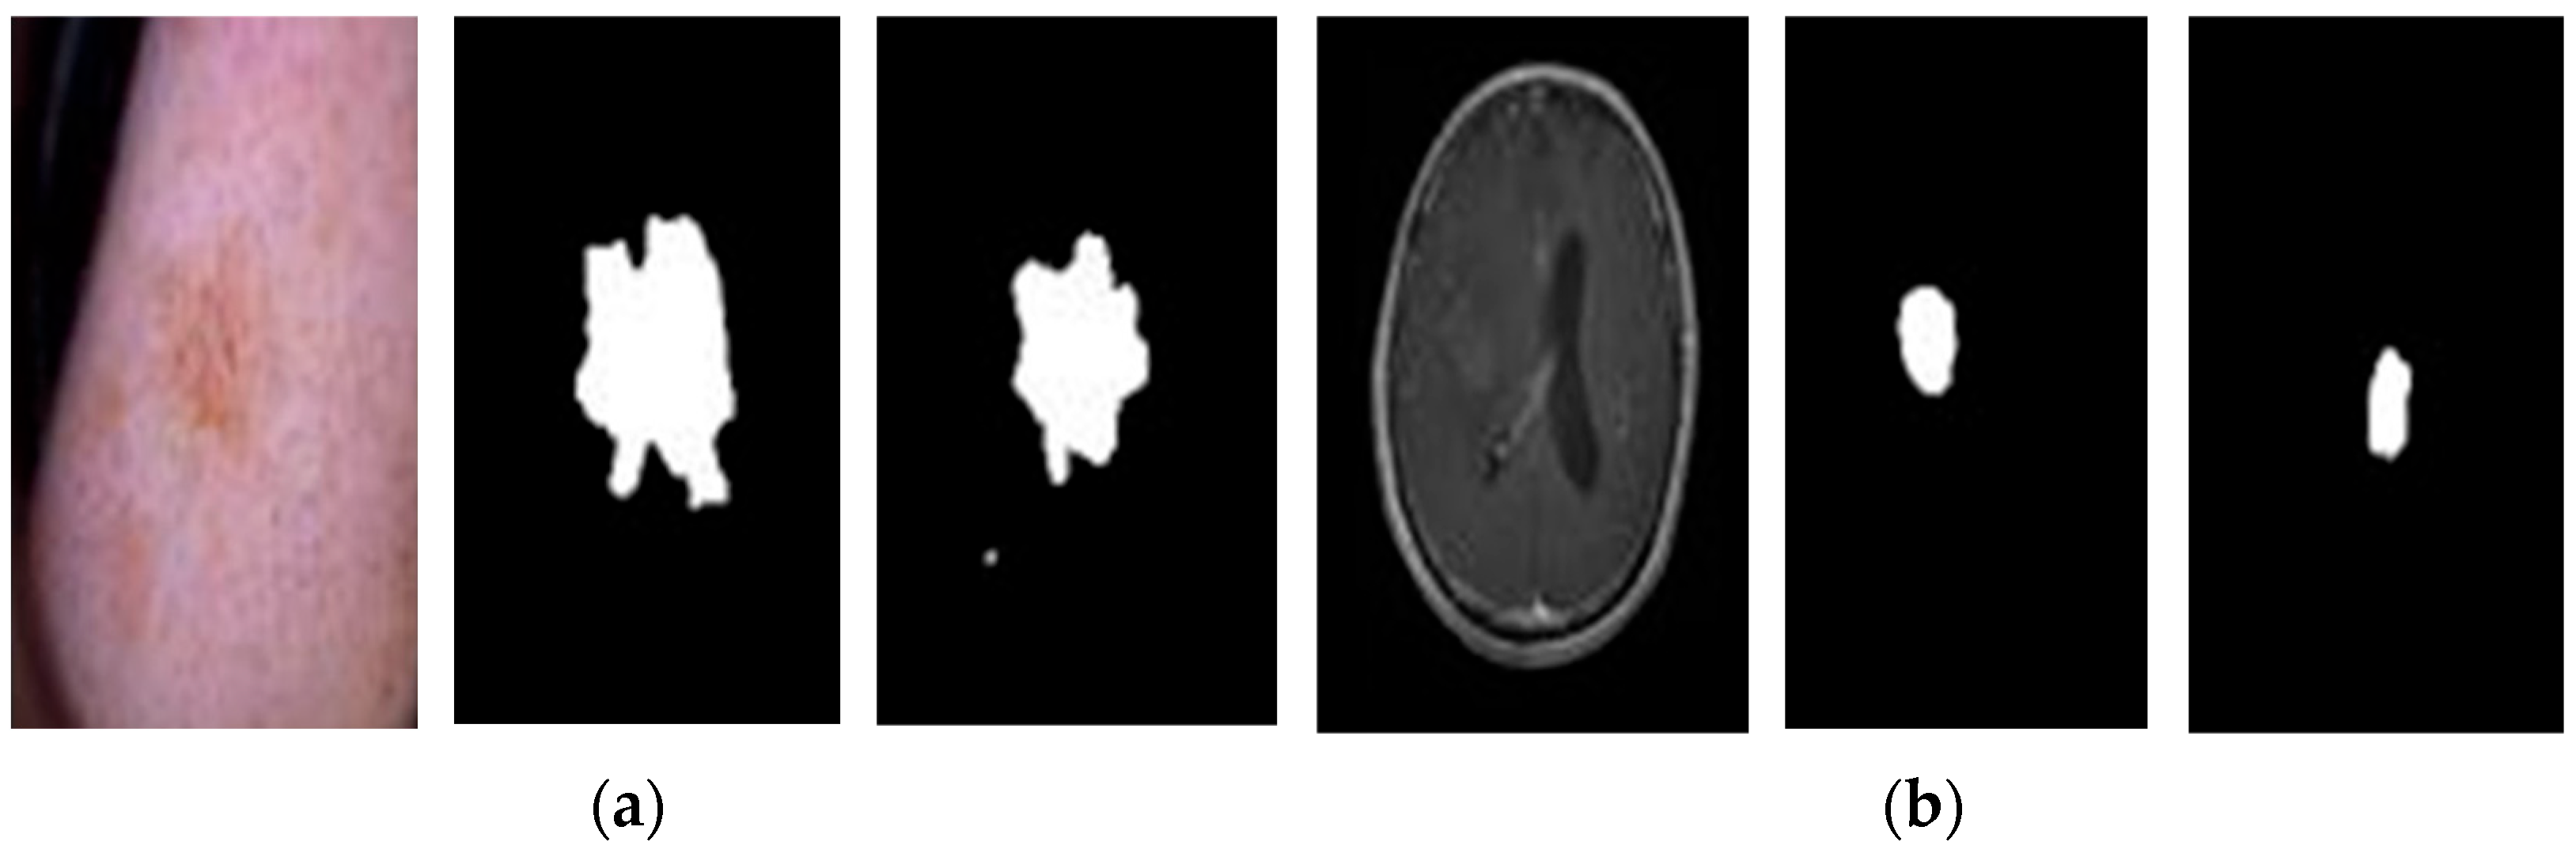

- U-Net Segmentation (described in Section 3.3): a U-Net architecture is employed to extract informative features from the preprocessed images. This segmentation step focuses on identifying the region of interest (ROI) within the image, which contains the potential cancerous tissue (skin lesion or brain tumor). This targeted approach allows the model to concentrate on the most relevant image area for classification. The segmentation results for sample images are illustrated in Figure 7, demonstrating the U-Net’s ability to identify potential problem regions.

- ROI Cropping: Following U-Net segmentation, the generated mask is used to crop the image to a smaller size (400 × 400 pixels), as demonstrated in Figure 11. This reduces the computational burden on the classification model without compromising essential information.